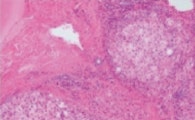

How does the Olympus True Color LED perform on real-world samples? To test this, the performance of the True Color LED was visually evaluated by direct comparison against other commercially available LED light sources on common histological stains: Hematoxylin and Eosin (H&E) and Azan Trichrome (figure 8).

Figure 8: Comparing LED Light Sources

Both in H&E-stained (a-d) and in Azan-stained tissue sections (e-h) True Color LED illumination shows no discernable color shifts compared to halogen lamp whereas other commercially available LED sources show distinctive yellow shifts (c and g) or blue shifts (d and h).